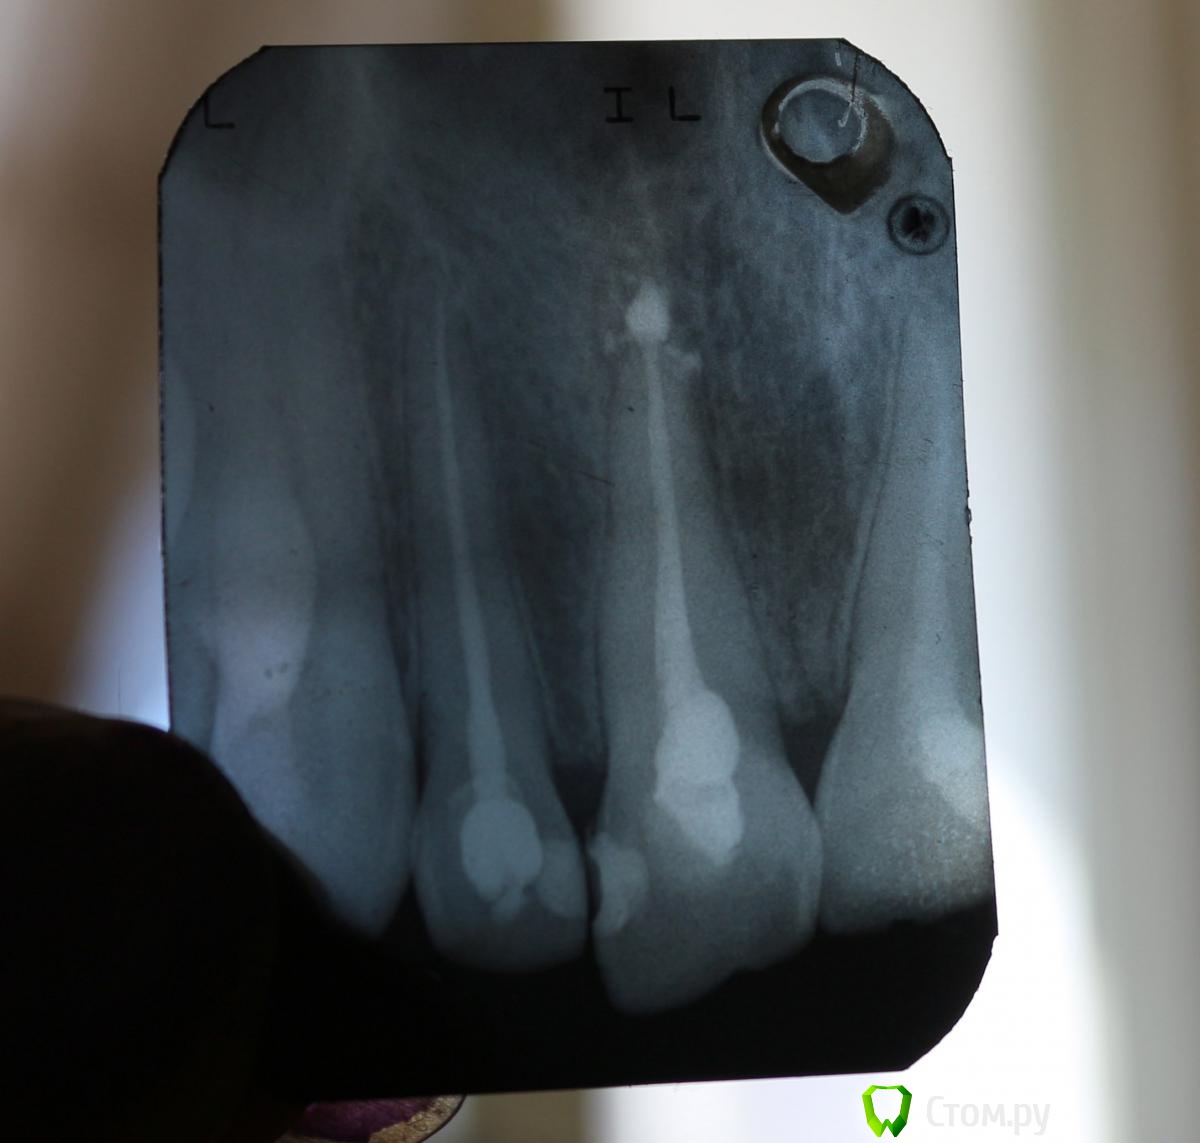

bmr Опубликовано 29 марта, 2014 Поделиться Опубликовано 29 марта, 2014 Здравствуйте. Воспалился передний зуб. Была сильная , рвущая боль. Ощущение выросшего зуба. Адская боль при накусывании. Пошел к врачу. Зуб вылечили, запломбировали. Врач сказал, что болевые ощущения пройдут в течение двух недель. Промучался месяц. Не прошли. Пошел к другому врачу. Зуб вскрыли. Внутри обнаружился гной. Пломбу поставили не герметично. По словам врача "только по краям намазали". Лечение проходило в несколько сеансов. Прочистили канал - отправили полоскать. Снова прочистили - снова полоскать. Поставили временную пломбу с лекарством на 4 дня. Затем поставили штифт и опять временную пломбу. После уже запломбировали полностью. Врач сказал, что вывел гуттаперчу за верхушку, чтобы не образовалась киста. Предупредил, что зуб должен "переболеть", но не уточнил сроки. Прошло 1, 5 месяца. Раньше по утрам зуб болел очень сильно. Боль сохранялась в течение пяти минут, потом уходила. Сейчас по утрам ее практически нет. Немножко болит не то, что даже при накусывании, скорее при мелком постукивании зубами. Если надавить сильно - боли нет.При постукивании по зубу ногтем тоже есть небольшие болезненные ощущения. Опять же, при ощутимом надавливании зубной щеткой боли тоже нет. Во время еды никак не мешает. Если его не беспокоить - тоже не тревожит особо, так, легкий дискомфорт. Посмотрите, пожалуйста снимки. Все ли верно сделал врач. Не стоит ли его перелечить?Зуб возможно воспалился вследствие травмы. Ударился передними зубами незадолго до этого. Врач что-то говорил о воспалении какого-то нерва, но я не помню, что конкретно. Как-то не обратил внимание. Не связано ли это с болью? Ссылка на комментарий

red_butler Опубликовано 29 марта, 2014 Поделиться Опубликовано 29 марта, 2014 выведен силер и штифт, если зуб будет беспокоить и дальше, потребуется хирургическое вмешательство для удаления пломбировочного материала Ссылка на комментарий

red_butler Опубликовано 29 марта, 2014 Поделиться Опубликовано 29 марта, 2014 По словам стоматолога это было сделано преднамерянно, чтобы не образовалась киста. Ранее над верхушкой зуба был гнойный мешок и омертвевшая ткань. Если пломбировочный материал уберут, не образуется ли киста? И если это не убрать, чем это грозит?Слова вашего стоматолога, о которых я узнал с Ваших слов, комментировать не буду. Лечение периодонта подразумевает полноценную механическую и медикаментозную обработку системы корневых каналов, с последующей обтурацией. Смысл снизить количество микроорганизмов до такого уровня, когда они не смогут оказывать патогенное действие. Выведение пломбировочного материала за верхушку корня может приводить к раздражение периапикальных тканей и воспалению 1 Ссылка на комментарий